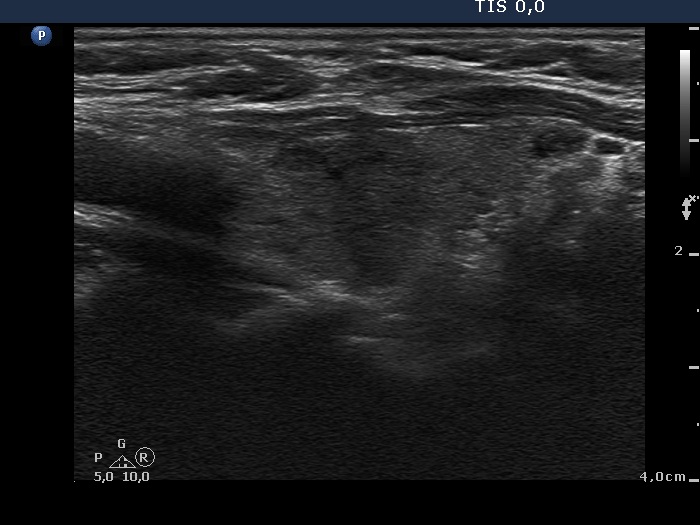

Discrete lesion or nodule in Hashimoto's thyroiditis - case 17 (782) (ultrasonographic picture 8)

Left lobe, longitudinal view. This hypoechogenic area has irregular shape and borders and therefore this is very likely not a pathological nodule.